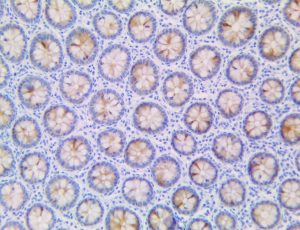

The first cytokines released are interleukin 1β (IL-1β) and tumor necrosis factor-α (TNF-α), which attract a variety of circulating white blood cells (WBCs) to the infection site, including neutrophils, monocytes, macrophages, and natural killer (NK) cells. This response, along with the antipathogenic chemicals released by these cells (i.e., complement), comprise the innate immune response. These cells directly attack the invading pathogen and also release additional cytokines, chief among them interleukin-1 and 6 (IL-6). IL-6 is essential for invoking the adaptive immune response, which calls T-cells, B-cells, and T helper (Th) cells to the infection site. IL-6 also stimulates further recruitment, proliferation and activation of macrophages.